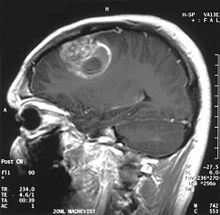

Glioblastoma - MR coronal with contrast.jpg

Coronal MRI with contrast of a glioblastoma in a 15-year-old male

Sagittal MRI with contrast of a glioblastoma WHO grade IV in a 15-year-old boy